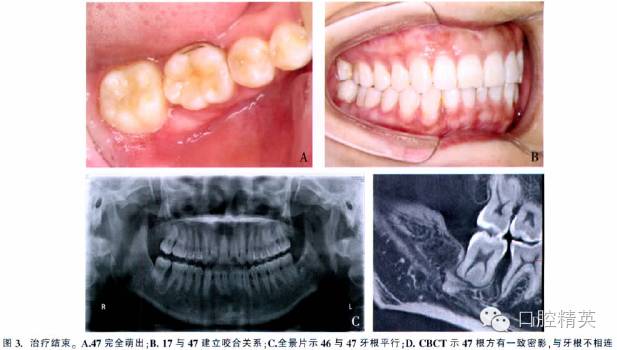

總療程為9.5個(gè)月。47牙周附著水平正常,與對(duì)牙合牙咬合關(guān)系良好。頭影測(cè)量顯示治療前、后下頜平面角和面下1/3高度無(wú)明顯變化。CBCT示右后牙牙根平行,47牙根長(zhǎng)度及根形未發(fā)生變化(圖3)。